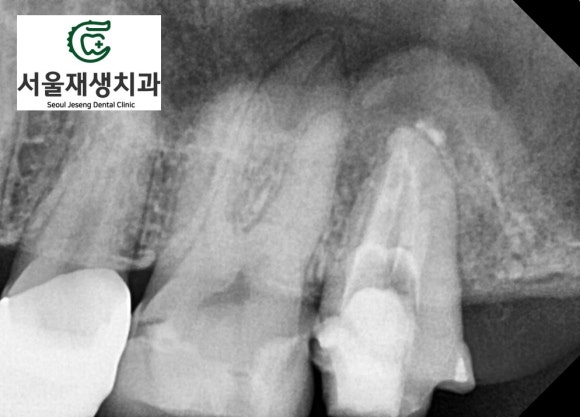

![[재신경치료] 예전에 신경치료 한 치아가 갑자기 붓고 아파요! (현미경 신경치료, 서울재생치과) 관련 이미지 5](https://pub-9f2bb3498faf4d1d8714b41df24753e3.r2.dev/content/clinics/archive/nqmm0udu86/naver_blog/honeybeevuvu/assets/by_hash/276a3eb18024b1408ac1f8f44336f5e0019d3700c9f9253de6861b919e85f318.jpg)

치과 검사의 가장 기본이 되는

파노라마 엑스레이입니다.

사진상으로 오른쪽 꼭대기에

심상치 않은 치아가 관찰됩니다.

![[재신경치료] 예전에 신경치료 한 치아가 갑자기 붓고 아파요! (현미경 신경치료, 서울재생치과) 관련 이미지 6](https://pub-9f2bb3498faf4d1d8714b41df24753e3.r2.dev/content/clinics/archive/nqmm0udu86/naver_blog/honeybeevuvu/assets/by_hash/b0676727a3c7282ad4a465de3a6df3a33116217f65e5f47d1cccc547ecd8d870.jpg)

신경치료가 아주 잘된 것 같은데요...

그런데 왜 뿌리 끝 주위의

뼈가 녹아있는 걸까요?